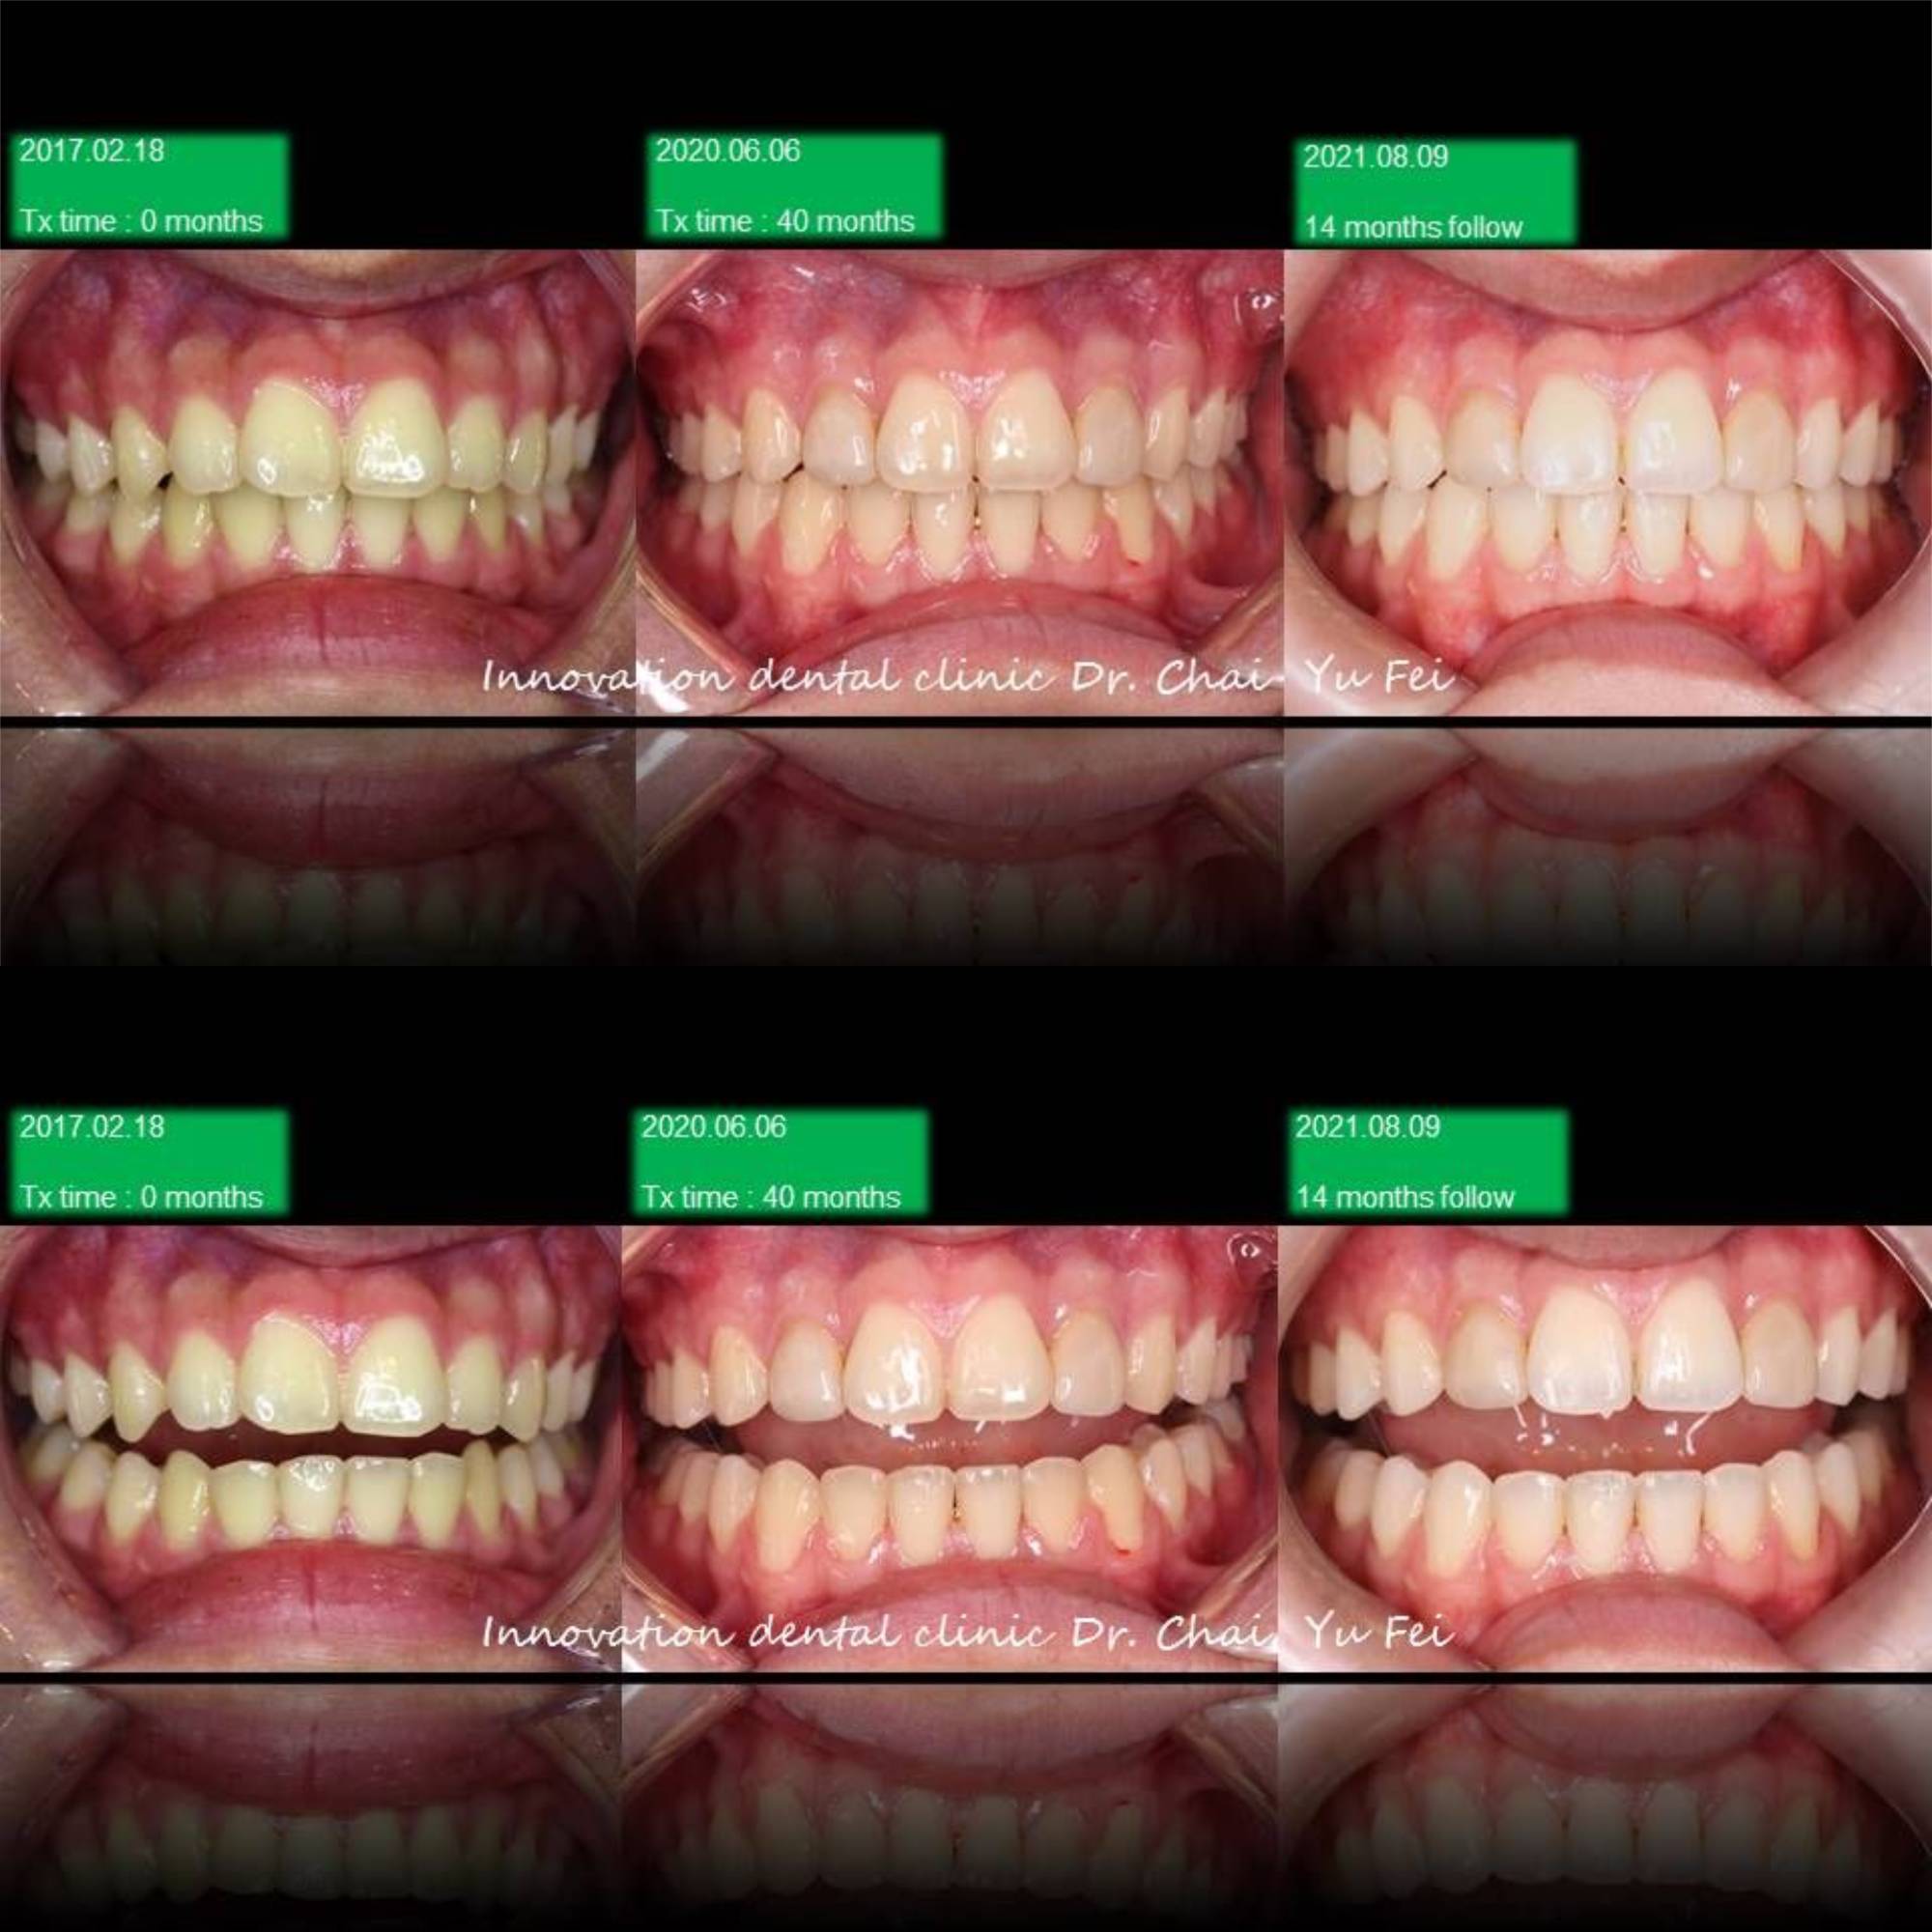

[ 治療方式 ] : 利用矯正 , 將前突的齒列內收,改善外觀,右側咬合高度喪失重建,植牙,恢復美觀功能

[ 治療時間 ] : 40 個月

男生的發育都是很長遠的,看到初始這樣的暴牙可能會擔心需要拔牙改善,但是考量孩子的年紀與生長潛力

我們採用上顎到後期用骨釘加一層保險去控制,下顎讓孩子自然生長的方式,現在這位高材生都已經升大學了

今年暑假回來follow 的成果讓人很感動

Non-extraction case .

Upper control by mini screw , lower let him grow automatically

很感謝他矯正期間的配合,很有耐心地讓我在最後改中線的部分花了不少時間。